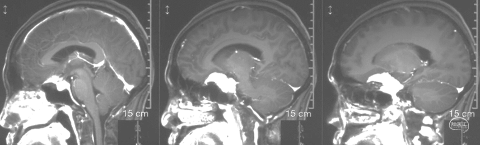

术前影像学检查

头颅MRI+增强